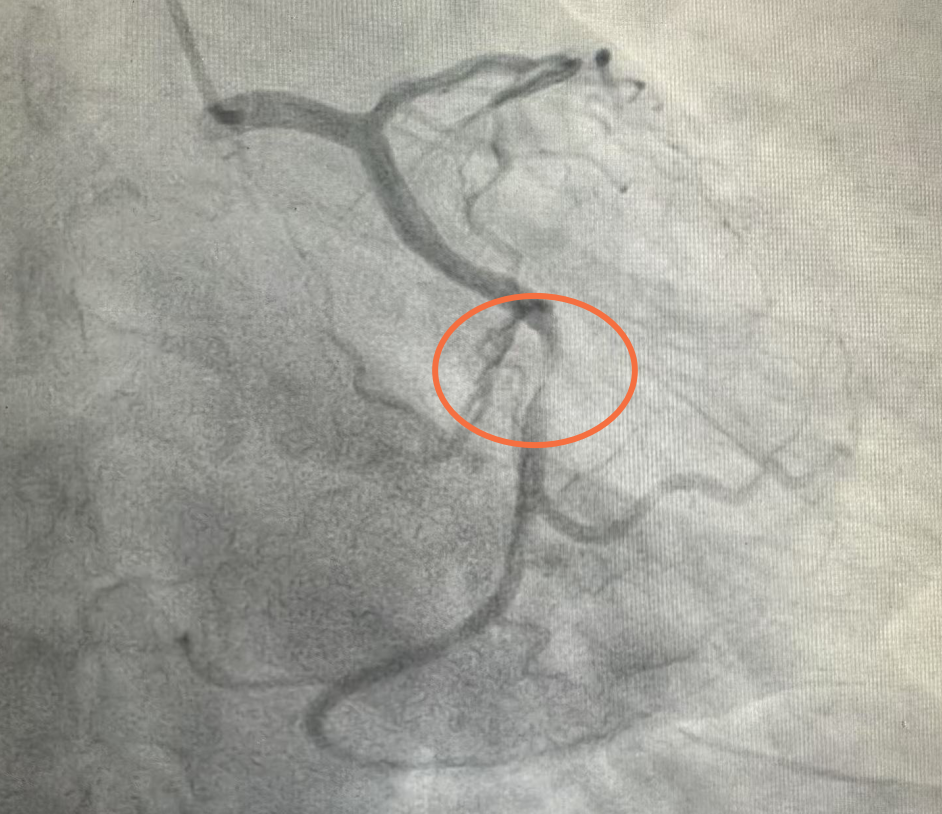

凌晨3点49分,患者到达医院急诊科,立即安排完成床旁心电图、心肌酶谱等检查,结合检查结果诊断为:急性心肌梗死;而冠状动脉造影影像显示,患者心脏的三条主要血管中,左回旋支中段竟有99%的狭窄,血管壁的病变处犹如定时炸弹,随时可能完全闭塞。"这就是引发心梗的'罪犯血管',必须立即开通!"吴志刚与介入团队迅速达成共识。与患者及家属充分沟通后,决定为患者行PCI(经皮冠状动脉介入术)治疗。

术前血管严重堵塞:

术后血管完全开通: